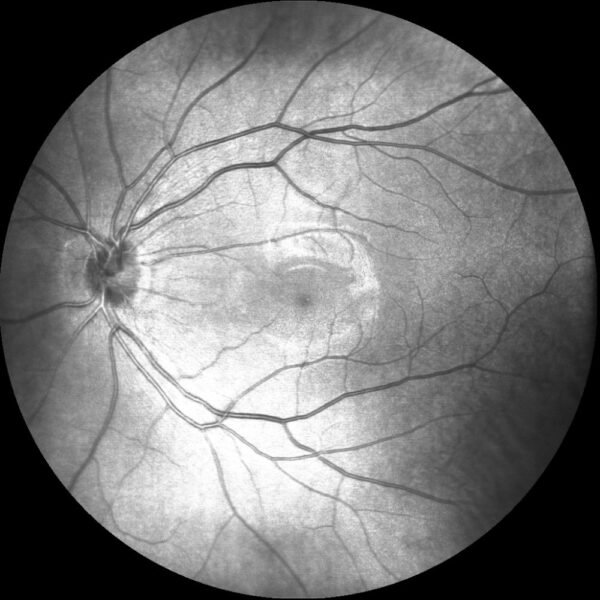

SLO-OCT e OCTA com VASCAN ADVANCE

O Mocean 4000 é configurado com os sistemas de imagens combinados SLO-OCT de ponta e o rastreador ocular baseado em SLO, uma plataforma poderosa para aplicações avançadas, como a angiografia OCT.